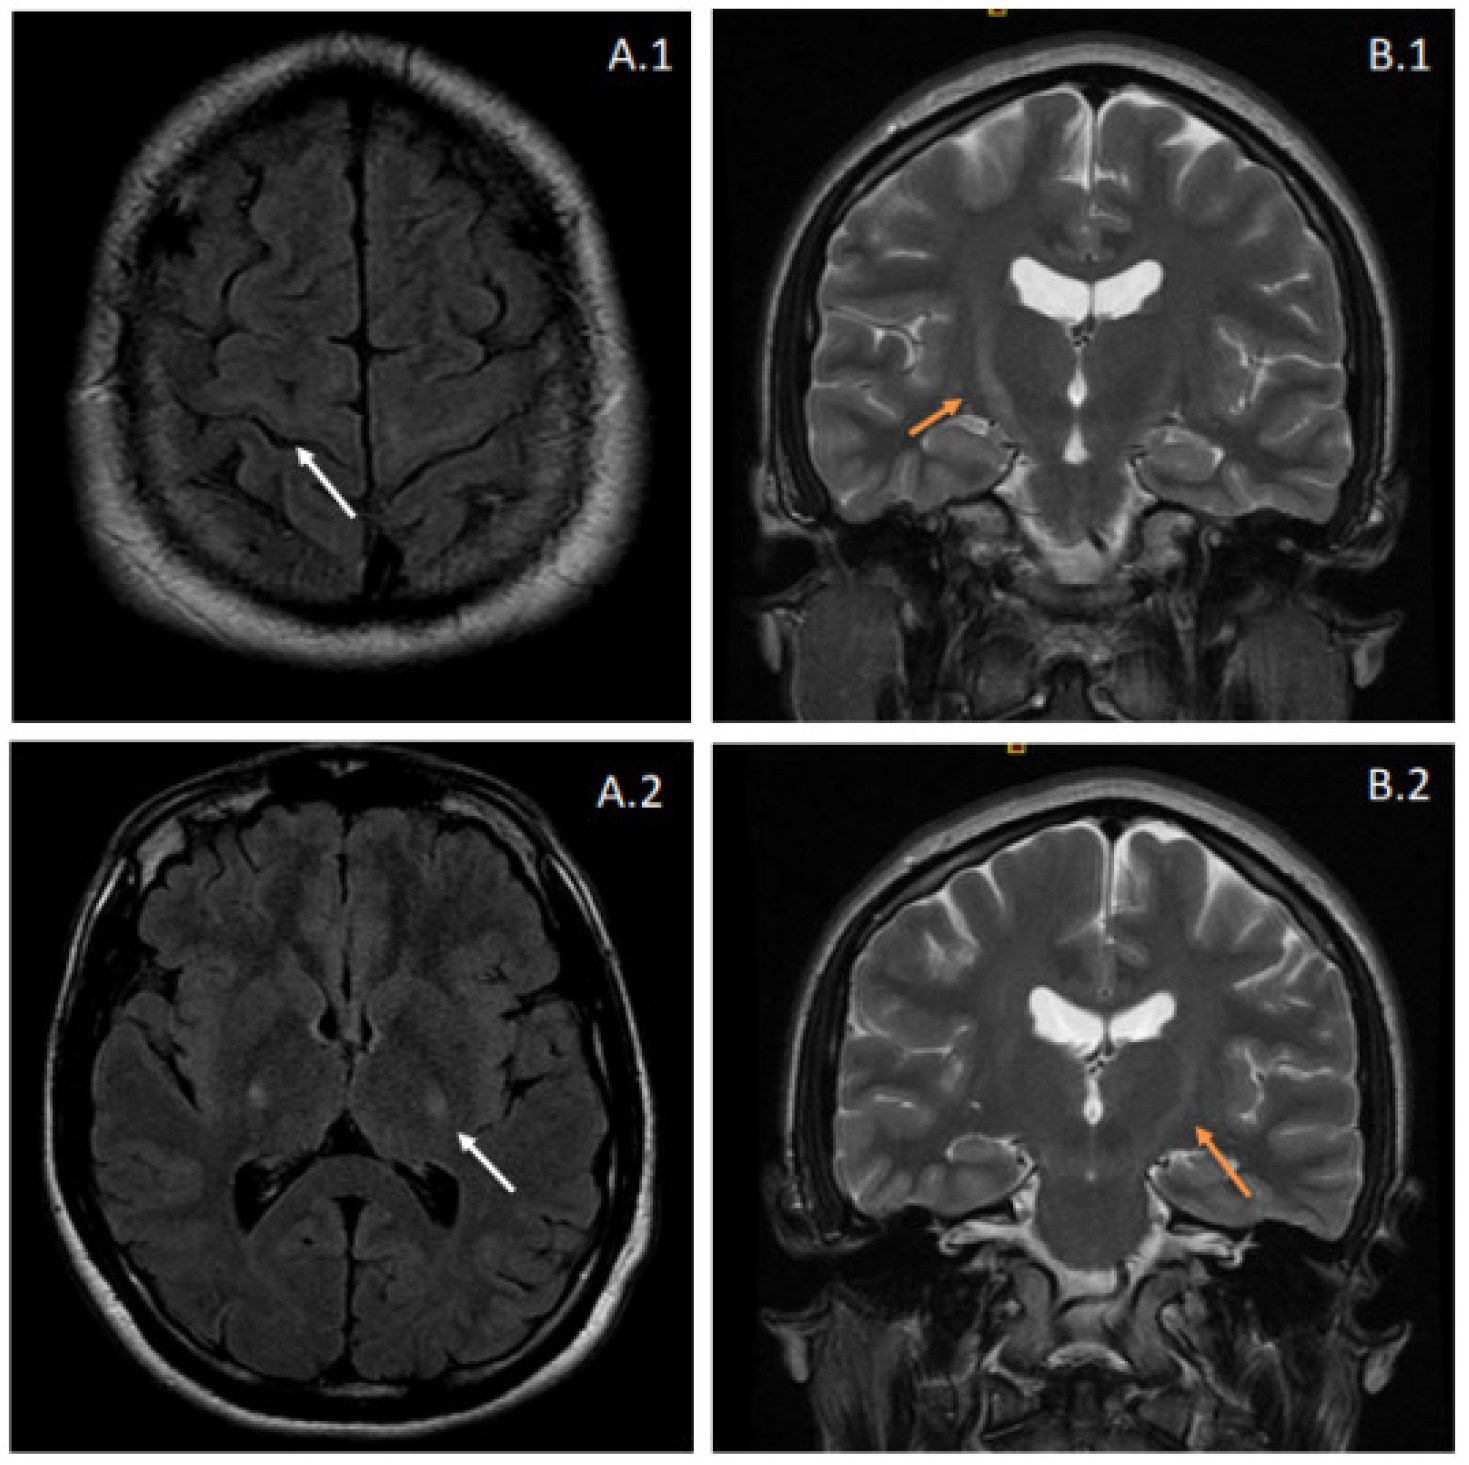

Brain and spinal magnetic resonance imaging (MRI) showed T2-weighted and fluid-attenuated inversion recovery (FLAIR) increased signal intensities at the pyramidal tracts bilaterally, suggestive of corticospinal pathway degeneration (Figure 1). The electrophysiological tests showed evidence of lower motor neuron involvement, with active denervation in lower extremity muscles in needle electromyography (tibialis anterior, vastus medialis, and gastrocnemius bilaterally) and a conduction defect in the corticospinal pathway in both upper and lower extremities using transcranial magnetic stimulation. Cerebrospinal fluid analysis was entirely normal. Further comprehensive laboratory workup ruled out other inflammatory or infectious causes.

Figure 1.

Brain MRI from the proband. Images (A.1,A.2) correspond to fluid-attenuated inversion recovery (FLAIR) sequences, showing hyperintensity affecting the pyramidal tracts bilaterally (white arrows). These features suggest degeneration of the corticospinal pathway and can also be observed in coronal T2-weighted images (B.1,B.2) as increased signal intensities at the internal capsule. The latter radiologic appearance is also known as the “Wine Glass” sign.